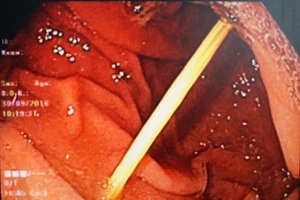

Suýt thủng dạ dày vì nuốt tăm khi uống nước

29/11/2016 15:54

Ăn bánh canh nuốt luôn tăm tre mà không biết

09/10/2016 10:59